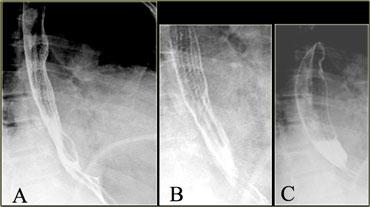

A. Co bóp bậc ba không có tính đẩy ban đầu B. Ba hình ảnh trong quá trình thăm khám cho thấy các ổ đọng thuốc giống túi thừa C. Hình ảnh chụp muộn hơn trong quá trình thăm khám cho thấy các co bóp bậc ba đã biến mất

Đôi khi các co bóp bậc ba thoáng qua có thể giả dạng túi thừa.

Bên trái là hình ảnh của một bệnh nhân có co bóp bậc ba, trong quá trình thăm khám trông giống như túi thừa.